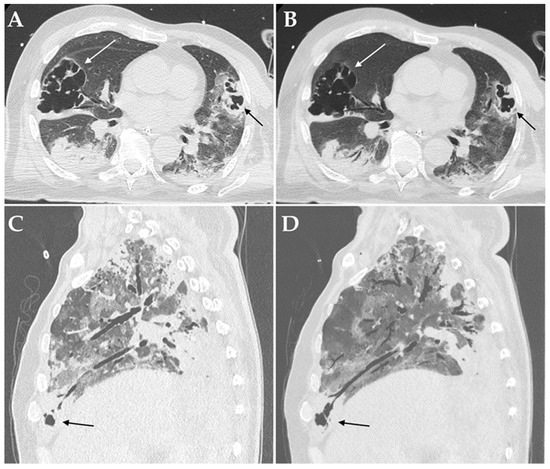

Figure 3.

Axial HRCT images of a patient admitted to ICU with confirmed superinfection by Aspergillus fumigatus showing pulmonary consolidations in the lower lobes complicated by bilateral cavitations (white and black arrows in (A)); Minimum Intensity Projection (MIP) reconstruction of the same patient demonstrating communication between the cavitations and the bronchial tree (white and black arrows in (B)). Sagittal HRCT images of a patient admitted to ICU with confirmed superinfection by Aspergillus niger showing pulmonary consolidations in the anterior-basal segment of the right lower lobe complicated by small cavitations (black arrow in (C)); Minimum Intensity Projection (MIP) reconstruction of the same patient demonstrating communication between the cavitation and the bronchial tree (black arrows in (D)).